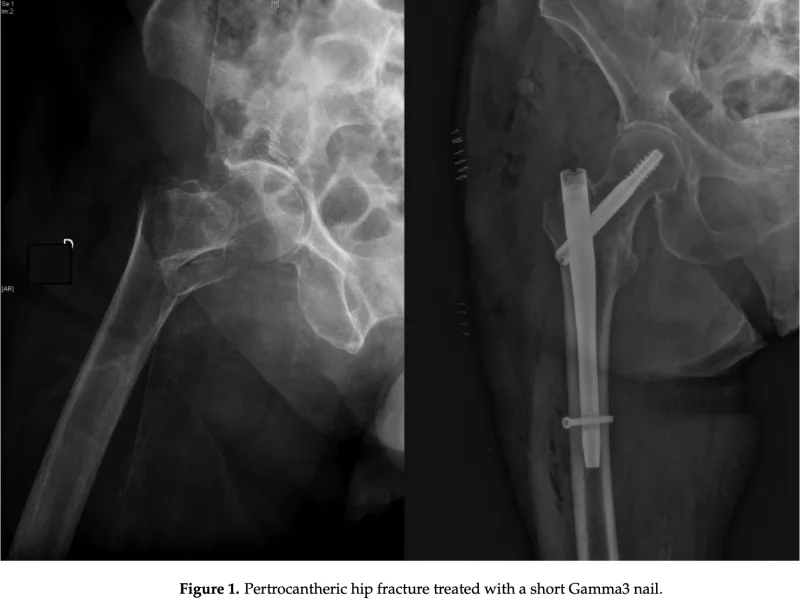

13時半から大腿骨転子部骨折に対する観血的手術を執刀.

今回は, Stryker社のガンマ4という器械を使用.

2023年6月に発売された新しい骨接合器械で, 2004年に発売されたガンマ3の改良型です.

手術の途中で大学病院から診療応援に来ていただいた整形外科研修1年目の後輩医師に交代して, ドリルで孔を開けて, ネジを入れてもらう操作を実施していただきました.

後輩医師の指導・育成も先輩医師の努めになります.

予定通り40分ほどで終了.